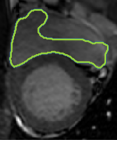

4.2 Visual assessment

We select the case that achieves the highest and lowest dice score for visual assessment. Fig. 4 shows example segmentation results where the proposed method achieved the highest agreement with the ground truth delineations. Fig. 5 shows example segmentation results where the proposed method achieved the lowest agreement with the ground truth delineations.